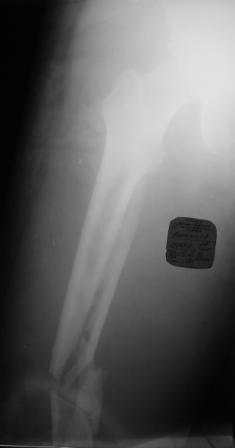

Хотелось узнать Ваше мнение по тактике лечения многооскольчатого перелома бедра Пациент 26 лет, травма в результате ДТП. Находится на системе скелетного вытяжения. Соматически уже компенсирован. Планируется выполнить остеосинтез бедренной LCP пластиной на тракционном столе, при этом не хотим обнажать зону многооскольчатого перелома. Буду благодарен за критические замечания по предложенной тактике и другие светлые мысли!

Выбор на пластине основан на том, что проксимальный отломок не цельный, по рентгенограмме видно, что в нём практически до малого вертела имеется осколок. Поэтому у меня опасения, что фиксация внутрикостного стержня в проксимальном отломке не будет достаточно стабильной.

Чем не устраивают реконструкционные и проксимальные гвозди, которые фиксируются вверху за шейку и головку бедра?

Александр, спасибо за идею! Попробую её реализовать. Наверное остановимся на длиной реконструктивной гамме

Мне кажется в данном случае будет более уместен не гамма, а обычный реконструктивный бедренный стержень.

В первую очередь мы бы посмотрели более пристально проксимальную часть бедра. Известно, что при переломах диафиза в 20% встречаются ипсилатеральные переломы шейки бедра.

А уже далее последует выбор имплантанта. Если есть ЭОП, то можно поставить гвоздь либо антеградно, либо ретроградно. Если ЭОПа нет, но есть LISS технология, то вполне уместно применить широкую пластину не открывая место перелома.

учитывая возраст предпочтительней реконструктивный стержень с фиксацией в шейку и головку,а гамма это практически не удаляемая конструкция.